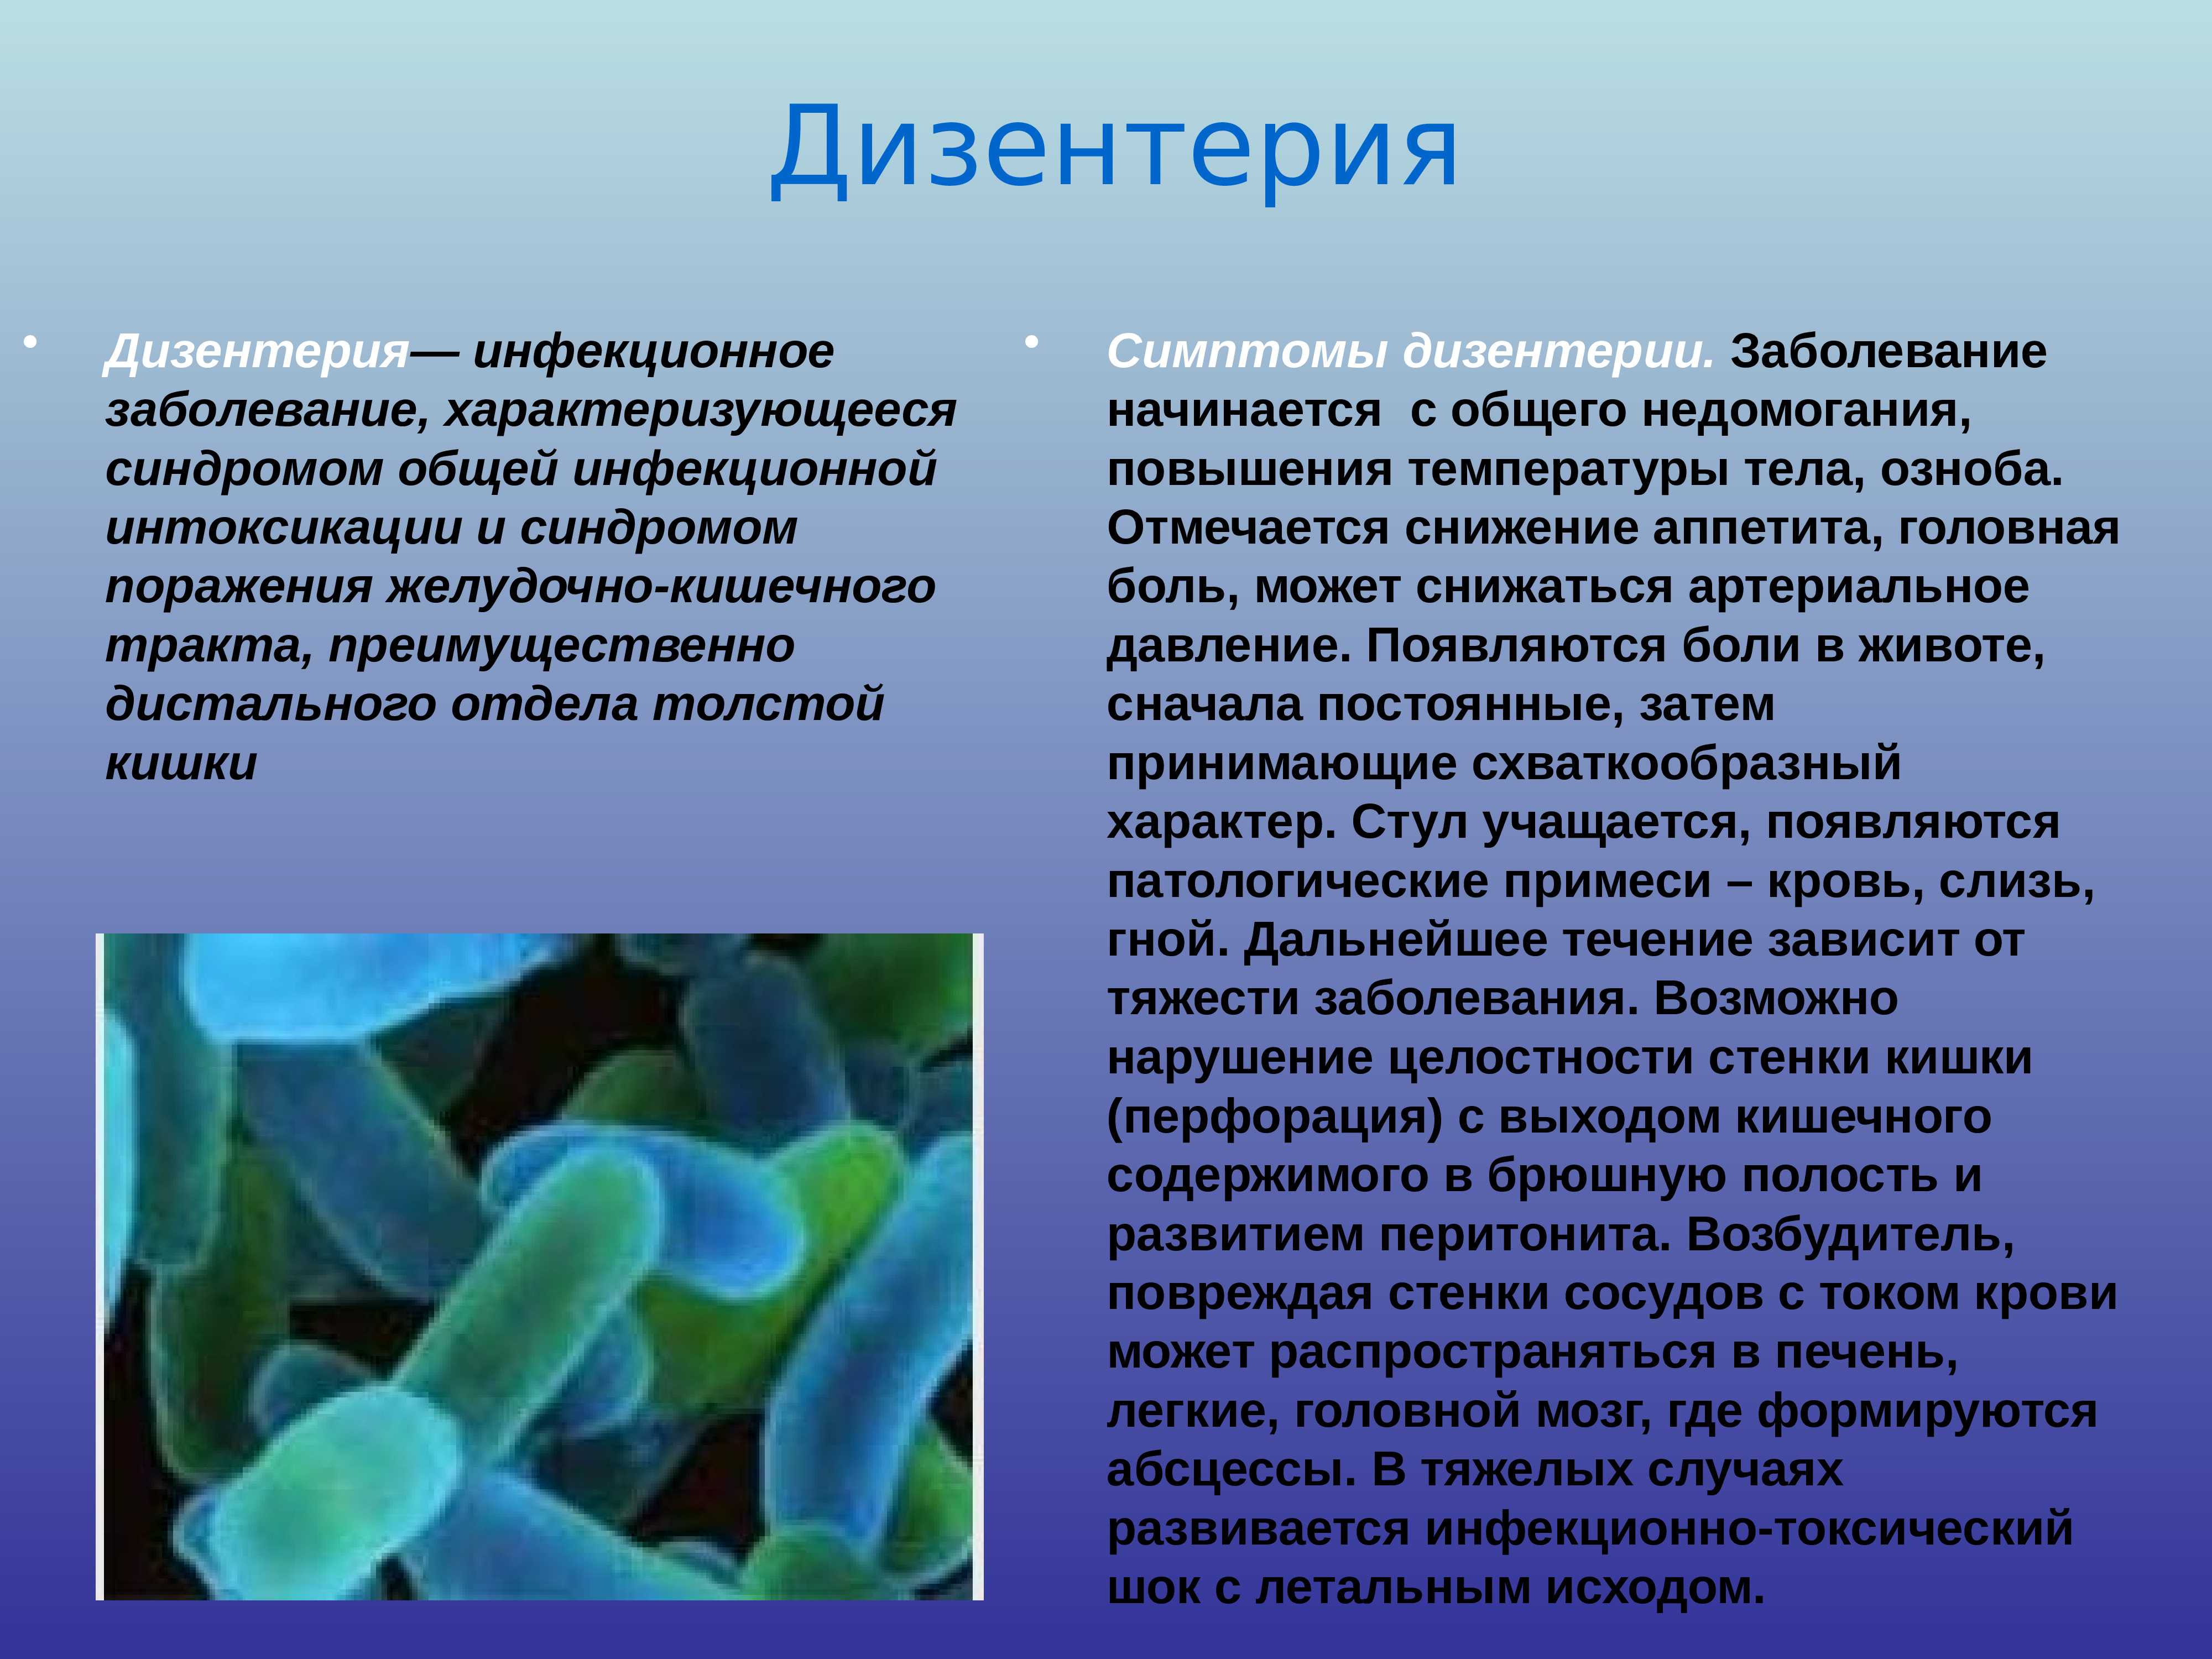

Диарея

Шигеллы дизентерии

Профилактика кишечных инфекций